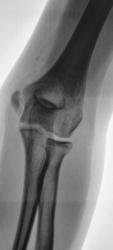

Другая рука "для сравнения". Прямая проекция.

Теперь все стало очевидным.

Другую руку бы посмотреть.

Другая рука для сравнения приведена - второй коммент в этой ветке - "Другая рука "для сравнения". Прямая проекция."

На здоровой руке обычная зона роста, на травмированной зона роста очень расширена. Это эпифизеолиз.